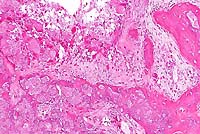

- Microscopic examination revealed a tumor-like mesenchymal

proliferation consisting of chondrocytes forming a rim of hyaline

cartilage surrounding spongy bone. The cortex of each growth

was irregular, and the spongy bone had trabeculae supporting

fatty marrow. Remnants of cartilage persisted in the osseous

mass. The histological picture suggests a peripheral chondromatous

proliferation followed by imperfect central endochondral ossification.

- Case 20-2. Bone. Irregular endochondral bone formation

occuring deep within cancellous bone. Dark cells in the lower

right are osteoclasts.

- Histologically, osteochondromas of dogs and horses recapitulate

the zones of development found in the normal epiphyseal growth

plate. Microscopic examination reveals a variably thick cartilage

cap with scattered areas of mineralization covered by a thin

layer of fibrous periosteum. The cap of hyaline cartilage is

bordered at the base by regularly arranged cancellous bone which

is produced by orderly endochondral ossification in actively

growing lesions. Trabeculae of cancellous bone are separated

by marrow elements. In old lesions in adult animals, extensive

endochondral ossification may result in little or no cartilage

remaining at the apical surface. Feline osteochondromatosis differs

microscopically from the inherited condition in young dogs and

horses in that the cartilage is irregular, chondrocytes are haphazardly

arranged, endochondral ossification is less orderly, and the

hyperplastic periosteum may directly form bone.